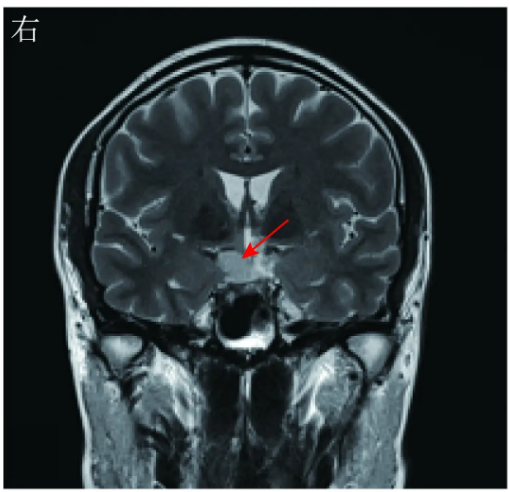

头颅MRI平扫示:鞍内垂体形态正常,鞍上区见不规则T1WI等信号、T2WI稍高信号影,大小约13 mm×17 mm(图2)。头颅增强MRI扫描示:鞍上区乏血供病灶,边缘清楚,结合MRI平扫结果考虑为鞍上区占位,表皮样囊肿可能(图3)。

图2术前头颅MRI冠状位平扫示,鞍上区不规则T1WI等信号、T2WI稍高信号影(红色箭头所示)

胶样囊肿的CT影像学表现多为等密度影或稍高密度影,少数呈低密度影。典型胶样囊肿的MRI影像学表现为T1WI呈高信号,T2WI呈等信号或低信号,边界清晰,增强MRI扫描见囊壁强化,内容物不强化。由于胶样囊肿内容物的成分(黏多糖、胆固醇和较高浓度的顺磁性物质)复杂,故MRI的影像学表现多样。本例患者头颅MRI显示的T1WI呈等信号、T2WI呈稍高信号,不完全符合上述常见的信号特点,可能与囊腔内黏多糖含量高等因素有关。